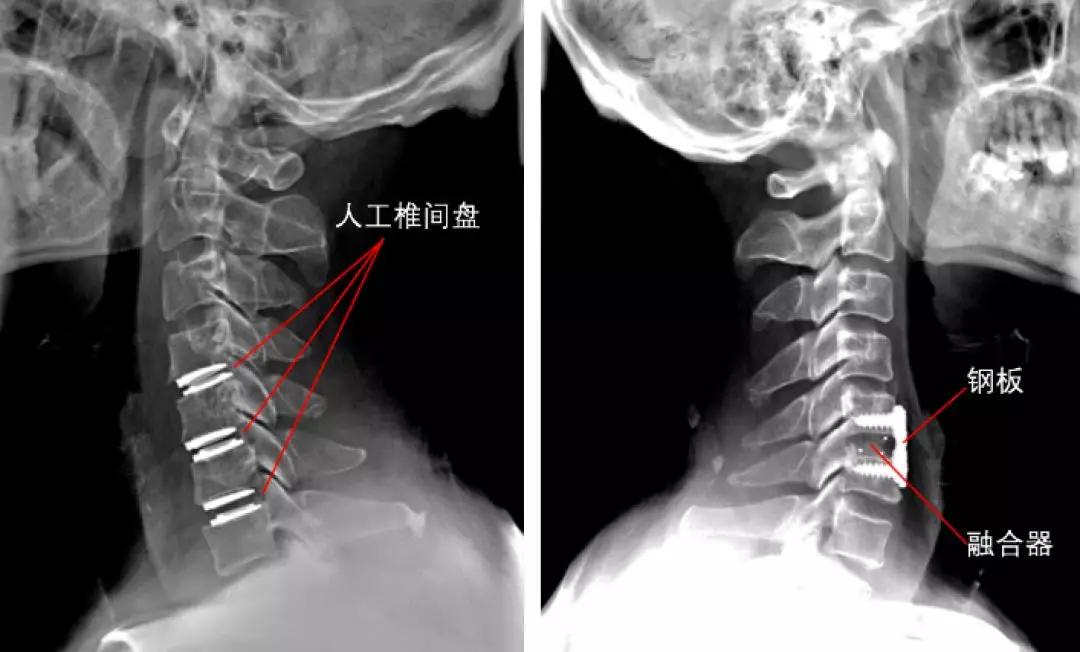

以颈椎前路手术为例,一般选择横切口,沿皮纹,左侧或右侧;

手术从肌肉间隙进入,将气管、食管牵开,很容易显露颈椎;

切开纤维环,用刮勺刮除椎间盘;

去除增生压迫神经及脊髓的骨赘;

安装椎间融合器;

钢板固定;

根据情况还可能选择人工椎间盘置换。